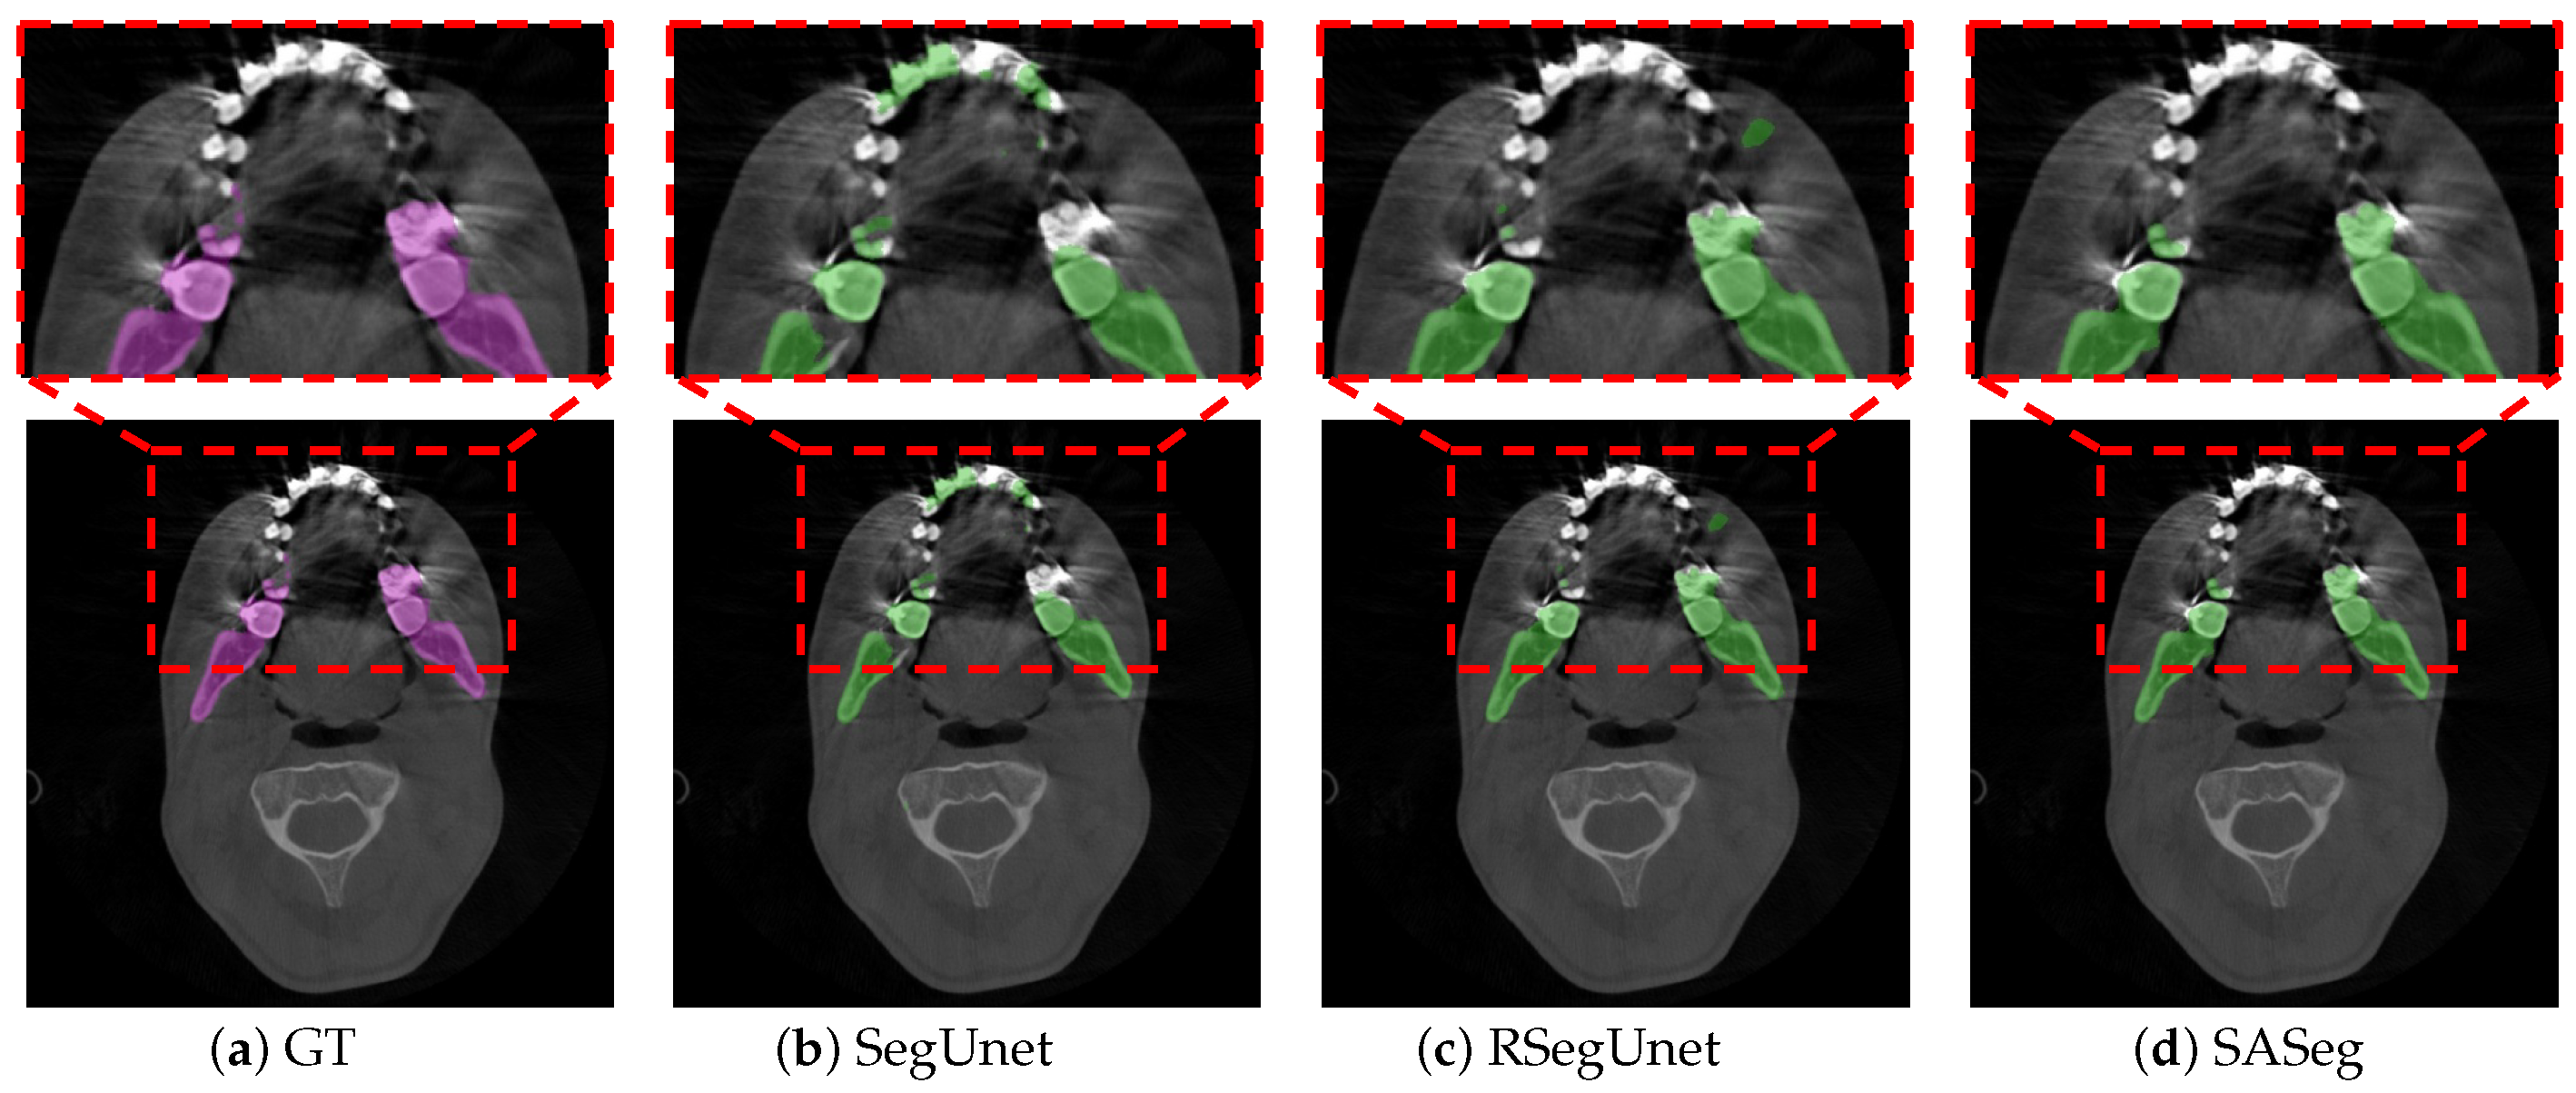

With the development of deep learning technology, deep learning methods have been proven to show powerful capabilities in detailed image feature extraction in automatic segmentation tasks [15,16,17]. The deep learning approach provides much more flexibility than the traditional methods [6,7,8,9,10], which require less expert analysis and fine-tuning and can easily exploit the other objects [18]. However, these studies [15,16,17] are still not robust in segmenting organs because the medical image usually has a 3D volume form, but 2D slices are usually fed as the input. For instance, Minnema et al. [13] employed a mixed-scale dense convolutional neural network to segment the mandible in CBCT. However, the other bone-structured organs are also segmented in this network, as shown in the figures of [13], due to the fact that the spatial information was not considered in their 2D network. To use 3D spatial information from the volume data, researchers first proposed to use a 3D network instead of the original 2D network. Çiçek et al. [19], Milletari et al. [20], Zhu et al. [21], and Wang et al. [22] explored a 3D convolution kernel in their network instead of the original 2D kernel in the medical image segmentation task. However, fully implementing the 3D network for image segmentation requires cropping the input volume into a small patch in training, which limits the maximum receptive field of the network and leads to the loss of global information. It is difficult for the 3D network to learn the overall structure information of the target. Thus, researchers started to investigate learning 3D spatial information and voxel connectivity of the upper and lower context of the object via a 2D network. Mortazi et al. [23] proposed the multiplanar training strategy, which utilized the images’ three perpendicular planes (axial, coronal, and sagittal) as input. Novikov et al. [24] used a sequence of slices as input in the network. Qiu et al. [12] adopted a 2.5D volume as input in their network and then combined the resulting 2D segmentations from three orthogonal planes into a 3D segmentation. Ghavami et al. [25] incorporated different numbers of neighboring slices as input for prostate segmentation from ultrasound images. Qiu et al. [26] developed a novel technique that combined a regular segmentation network with a recurrent module in their network for mandible segmentation in conventional CT scans. In general, these works [12,23,24,25,26] have shown that using adjacent slices can help the network obtain more accurate and reliable results in terms of anatomy. Nevertheless, these works [12,23,24,25,26] have also shown that obtaining 3D spatial information from a 2D network still leaves room for improvement. As illustrated in Figure 2, an example shows the comparison between SegUnet [27], recurrent SegUnet (RSegUnet) [26] and the proposed method in mandible segmentation. These methods are not suitable for CBCT images that are strongly corrupted by the metal braces and low contract due to the inherent characteristic of CBCT.

Figure 2. An example illustration that shows the comparison with SegUnet and RSegUnet. The existing state-of-the-art convolutional neural network (CNN) approaches for segmentation tasks perform poorly when the input data are strongly degenerated by noise. (a) the ground truth segmentation; (bd) the automatic segmentation results obtained from SegUnet [27], RSegUnet [26] and the proposed SASeg. The purple region indicates the manual annotation, while the green regions indicate automatic segmentations.